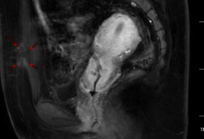

整個治療過程持續(xù)78分鐘,術后造影及核磁共振檢查顯示消融效果良好。術后第二天孫女士便順利出院,之后每逢月經來潮,既往的痛感明顯減輕。

術后增強核磁共振影像